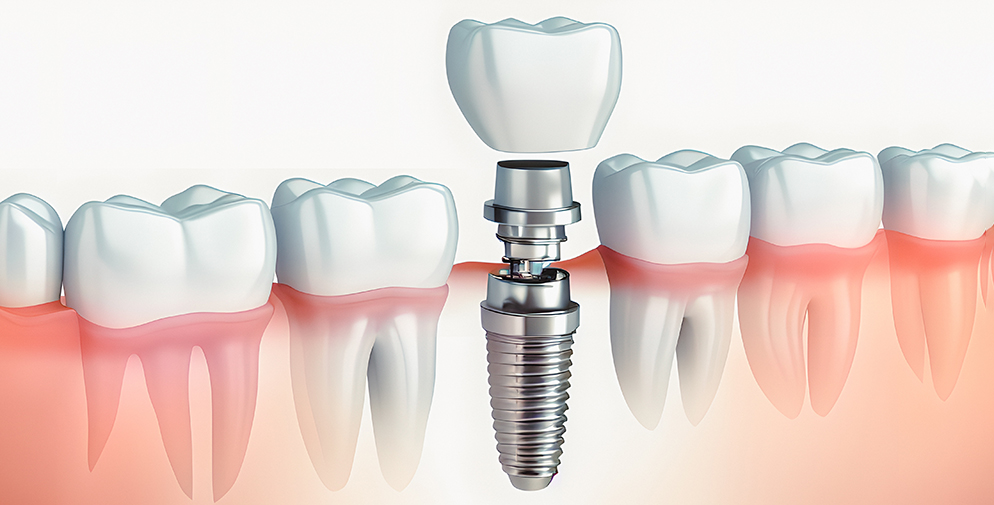

インプラント治療とは、歯を失ってしまった時に行う治療法の一つです。人工の歯根(歯の骨に植っている部分)を顎の骨に埋め込み、その上に人工的な歯(アバットメント+人工歯)を取り付ける構造になっています。その他取り外し式の入れ歯や両隣の歯を削って橋をかけるように固定するブリッジという方法もありますが全く異なる治療法となっています。

インプラント治療とブリッジなどの被せ物治療の一番の違いは、歯根(歯の根元)の有無となります。被せ物は残っている歯根に土台を入れ、その上に人工の歯を被せる治療法です。そのため、歯根(歯の根本)が残っていなければできないのです。

一方、インプラント治療は、歯を抜いた箇所(歯根が残っていない部分)に人工の歯根(インプラント)を埋め込み、上部構造(人工歯)を装着する治療法です。